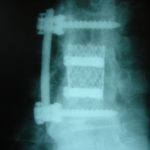

- α

- β

- γ

- δ

Εικ. 6: Μετεγχειρητικές ακτινογραφίες (α,β) 3 και (γ,δ) 9 έτη μετά την επέμβαση

Παρατηρείται η σταθερότητα της σπονδυλικής στήλης και η ακεραιότητα των υλικών